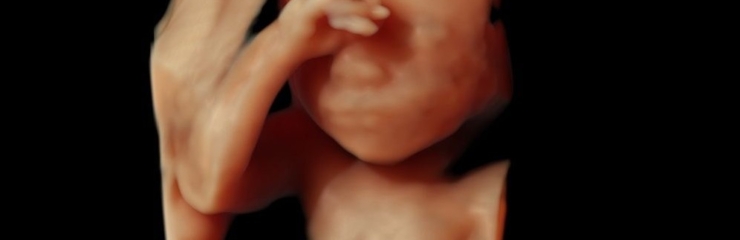

Loode:

Loote luud hakkavad tugevnema. Kopsudes moodustub aine, mis hingama hakkamisel aitab kopsudel avaneda. Loode teeb regulaarseid hingamisliigutusi. Loote nahk muutub vähem läbipaistvaks. Loote silmad reageerivad valgusele. Loote nahk on kortsuline ja tumepunane. Loote lõug muutub ümaramaks ning jalalaba suurus on umbes 2 sentimeetrit.

Loote kaal on umbes 1 kilogramm ja ta on 35 sentimeetri pikkune. See on parim aeg 4D ultraheliuuringu käigus loote näo vaatamiseks.

Mees:

See on aeg, mil võiks hakata tasapisi mõtlema sünnituse peale ja uurida, keda sooviks naine sünnitusele tugiisikuks. Sel ajal on võimalik koos käia ka 4D ultraheliuuringul, mis annab infot lapse tervise ja arengu kohta ning võimaldab tulevastel lapsevanematel jälgida reaalajas oma lapse tegevust, tekitades elevust ja pakkudes positiivseid emotsioone.

Uuringud:

- Vajadusel glükoositaluvuse test (24.-28. nädalal)

- Uriini- ja vereanalüüsid

- Naise kaalumine, kaaluiive hindamine

- Vererõhu ja emakapõhja kõrguse mõõtmine

- Tursete esinemise jälgimine

- Soovi korral 4D ultraheliuuring